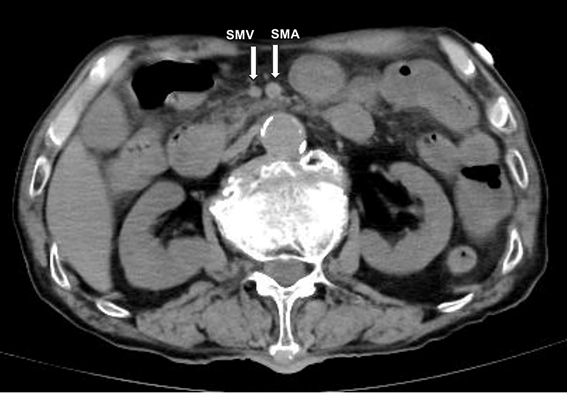

Figure 3. 腹部CTで認められた上腸間膜静脈の狭小化。急性腸間膜虚血を示唆する。

当初はCOVID-19肺炎が疑われたが、胸部CTでは肺炎像はなく、腹部CTで腸間膜虚血が見つかった。